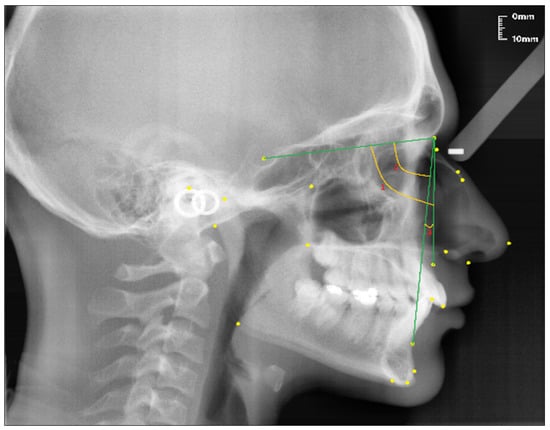

Figure 4.

Angular craniofacial skeletal measurements used in the study.

- SNA (°); the angle between the SN line and the NA line.

- SNB (°); the angle between the SN line and the NB line.

- ANB (°); the angle between the lines NA and NB.